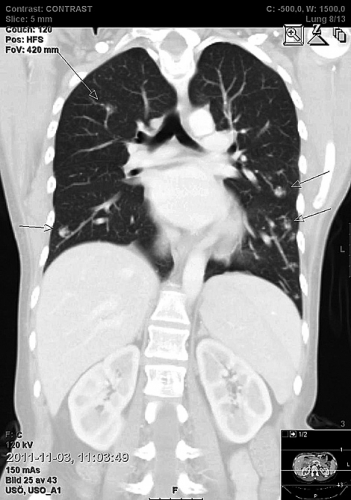

Tre år senare (i samband med att denna artikel skrevs) inkom patienten akut med epileptiska kramper sekundärt till en ny hjärnabscess. Denna gång skickades en remiss till Sveriges centrum för Mb Osler, lungkliniken vid Akademiska sjukhuset i Uppsala. Beslut togs nu om att embolisera de största arteriovenösa missbildningarna (Figur 2).

Förekomst av pulmonella arteriovenösa missbildningar spelar en avgörande roll för uppkomsten av hjärnabscesser och cerebrala händelser. Kapillärnätet i lungorna har normalt en filtrerande funktion för embolier och bakterier, men vid missbildningar kan blodet via lungorna shuntas ut till stora kretsloppet och nå den cerebrala cirkulationen. Pulmonella arteriovenösa missbildningar kan emboliseras, och om alla missbildningar ockluderas framgångsrikt är det visat att risken för hjärnabscess och ischemisk stroke minskar [6].

Sammanfattningsvis löper patienter med Mb Osler ökad risk att drabbas av allvarliga infektioner och andra livshotande komplikationer. Intracerebrala infektioner går att förebygga genom embolisering av pulmonella arteriovenösa missbildningar. Det rekommenderas därför internationellt att patienterna screenas med avseende på arteriovenös missbildning i lungan [7]. Enklast görs detta med DT-undersökning eller kontrastekokardiografi. Extracerebrala infektioner är svårare att förebygga eftersom det ännu inte finns några säkra riskfaktorer identifierade.